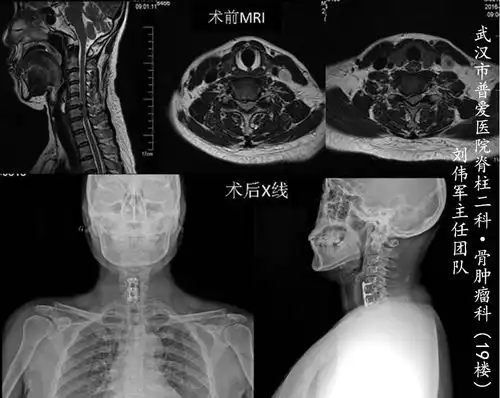

刘主任主刀,颈椎病患者前路手术展示